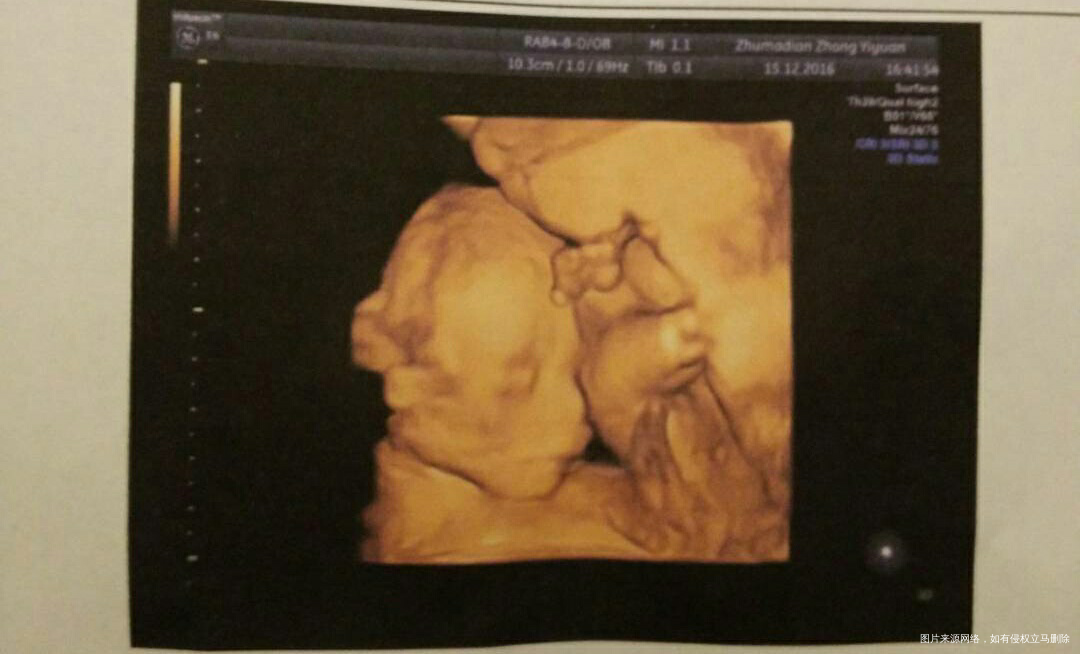

我们宝宝还没出生的时候,去照四维,相片一出来,他爸看的高兴的不行,说你快看,咱儿子的鼻子多像我!看那个尖!哈哈,我老公是有点鹰钩鼻的那种,所以鼻子真的很明显~[大笑][大笑]